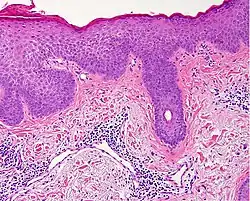

| Lichen planus | Irregular epidermal hyperplasia with a jagged “sawtooth” appearance, compact hyperkeratosis or orthokeratosis, foci of wedge-shaped hypergranulosis, basilar vacuolar degeneration, slight spongiosis in the spinous layer, and squamatization. The dermal papillae between the elongated rete ridges are frequently dome shaped. Necrotic keratinocytes can be observed in the basal layer of the epidermis and at the dermal-epidermal junction. Eosinophilic remnants of anucleate apoptotic basal cells may also be found in the dermis and are referred to as “colloid or civatte bodies”. Whickham striae are usually seen in the areas of hypergranulosis. Vacuolar degeneration at the basal layer may be noted leading to focal subepidermal clefts (Max Joseph spaces). Squamatization occurs as a result of maturation and flattening of cells in the basal layer. It happens in areas of marked hypergranulosis with prominence of the sawtooth pattern of rete ridges. Wedge-shaped hypergranulosis can occur in the eccrine ducts (acrosyringia) or hair follicles (acrotrichia). In the hypertrophic subtype, the associated hyperkeratosis, parakeratosis, hypergranulosis, papillomatosis, acanthosis, and hyperplasia markedly increased with thicker collagen bundles forming in the dermis. Moreover, the rete ridges are more elongated and rounded as opposed to the typical sawtooth pattern. In atrophic LP, loss of the rete ridges and dermal fibrosis is prominent. In vesiculobullous LP, the disease progression is quicker. Hence, some of the distinctive features such as hyperkeratosis, hypergranulosis, or dense lymphocytic dermal-epidermal infiltrate may not be present. LP lesion may resolve with residual hyperpigmentation caused by a persistent increase in the number of melanophages in the papillary dermis.[9] | ![]() |

|